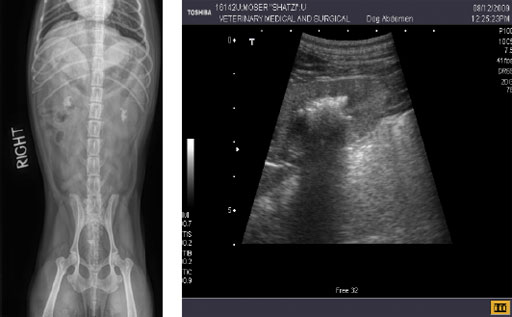

С помощью рентгена брюшной полости можно увидеть контрастные камни в почках и их расположение.

УЗИ брюшной полости полезно при оценке структуры почки, мочевого пузыря и подтверждает наличие, размер и количество почечных камней.